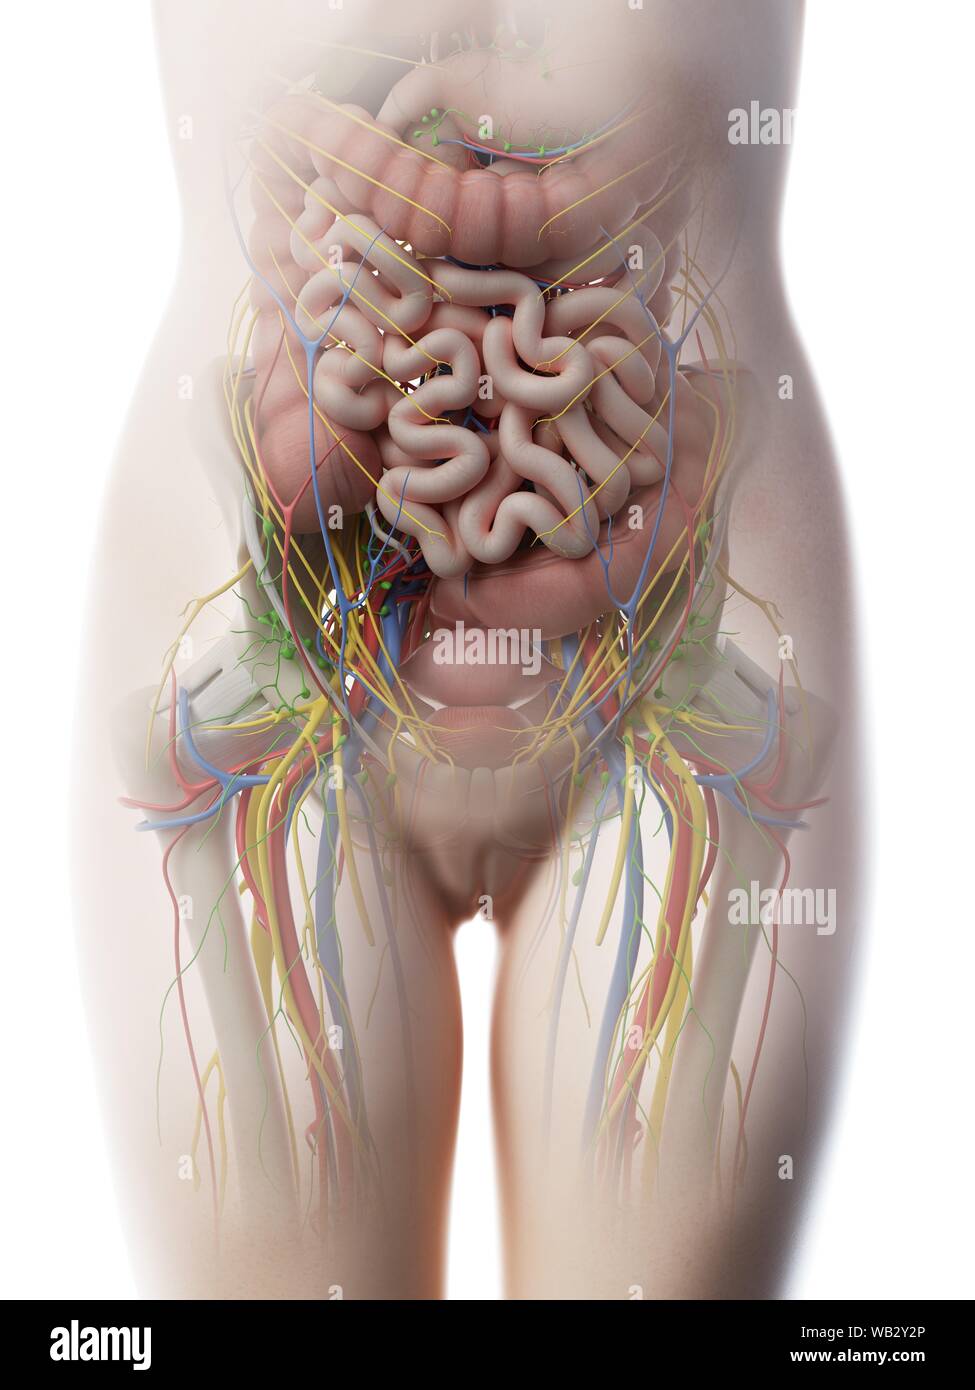

Anatomie de l'abdomen femelle, illustration de l'ordinateur. Banque D'Imageshttps://www.alamyimages.fr/image-license-details/?v=1https://www.alamyimages.fr/anatomie-de-l-abdomen-femelle-illustration-de-l-ordinateur-image264981899.html

Anatomie de l'abdomen femelle, illustration de l'ordinateur. Banque D'Imageshttps://www.alamyimages.fr/image-license-details/?v=1https://www.alamyimages.fr/anatomie-de-l-abdomen-femelle-illustration-de-l-ordinateur-image264981899.htmlRFWB2Y37–Anatomie de l'abdomen femelle, illustration de l'ordinateur.

Anatomie de l'abdomen femelle, illustration de l'ordinateur. Banque D'Imageshttps://www.alamyimages.fr/image-license-details/?v=1https://www.alamyimages.fr/anatomie-de-l-abdomen-femelle-illustration-de-l-ordinateur-image264981886.html

Anatomie de l'abdomen femelle, illustration de l'ordinateur. Banque D'Imageshttps://www.alamyimages.fr/image-license-details/?v=1https://www.alamyimages.fr/anatomie-de-l-abdomen-femelle-illustration-de-l-ordinateur-image264981886.htmlRFWB2Y2P–Anatomie de l'abdomen femelle, illustration de l'ordinateur.

Anatomie de l'abdomen femelle, illustration de l'ordinateur. Banque D'Imageshttps://www.alamyimages.fr/image-license-details/?v=1https://www.alamyimages.fr/anatomie-de-l-abdomen-femelle-illustration-de-l-ordinateur-image264981894.html

Anatomie de l'abdomen femelle, illustration de l'ordinateur. Banque D'Imageshttps://www.alamyimages.fr/image-license-details/?v=1https://www.alamyimages.fr/anatomie-de-l-abdomen-femelle-illustration-de-l-ordinateur-image264981894.htmlRFWB2Y32–Anatomie de l'abdomen femelle, illustration de l'ordinateur.